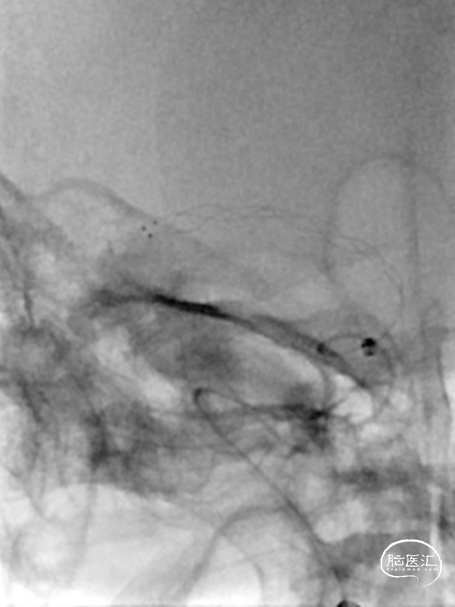

造影见RICA再通,RMCA M1段近端重度狭窄,约90%。

观察10分钟后,狭窄较前加重,局部不规则充盈缺损。术中即刻DynaCT未见造影剂染色。

将Synchro(0.014×300cm)微导丝外衬Gateway(2.0×15mm)球囊缓慢通过RMCA M1段狭窄处,球囊定位于RMCA狭窄处缓慢扩张,压力6atm。采用交换技术置入灌注微导管,并将4.0×16mm支架定位于狭窄处释放。